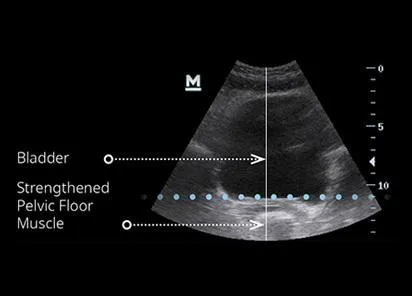

The pelvic floor muscles play a crucial role in supporting the bladder and maintaining continence. They help keep the urethra closed during daily activities — preventing leaks when you cough, laugh, sneeze, or exercise.

When these muscles weaken, it becomes harder to control bladder pressure, leading to stress or urge incontinence. Strengthening them through EMSELLA treatments improves muscle tone, coordination, and bladder support — helping reduce leaks naturally, comfortably, and without medication.